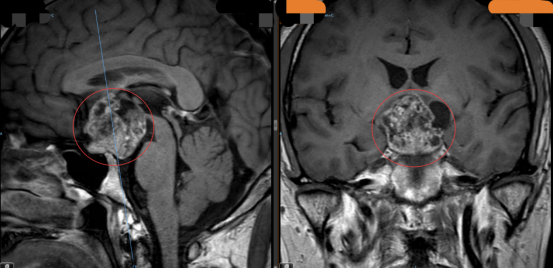

数月前,一场突如其来的“异常”打破了唐先生的正常生活——无明显诱因下,他频繁出现视物模糊,烦渴尿多等 症状……经磁共振检查,一个令人揪心的结果浮出水面:唐先生颅内长有一颗3.8×3.6×3.3 厘米的颅咽管瘤,而这颗“不速之客”正悄然威胁着他的生命健康。

(图中圈红位置为颅咽管瘤)

唐先生与家人辗转奔波于国内、省内多家大型医院,却屡屡碰壁。原来,这颗颅咽管瘤不仅体积庞大,更像一颗“定时炸弹”,深踞颅内最核心的要害区域,紧密缠绕着重要的血管与神经组织,手术操作空间狭窄如缝,稍有不慎便可能引发致命风险,若行传统开颅手术,创伤大、风险高。